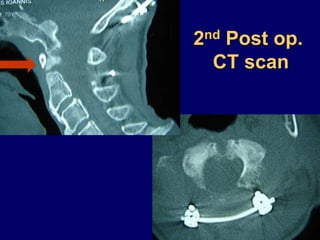

2nd Post op.

CT scan

Post op.